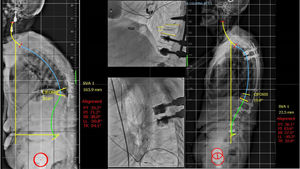

En el grupo de cifosis angular flexible compensada (1A C), si presenta un trazo estable se puede realizar una vertebroplastia (VP)/cifoplastia (KP) para hacer una corrección de la cifosis flexible y dar estabilidad anterior. En caso de una afectación del muro posterior o fractura de pedículos, que traduzcan inestabilidad, habría que añadir una instrumentación cementada corta para aportar la estabilidad7. En el caso de que la cifosis angular flexible no está compensada (1A NC) y exista un desequilibrio sagital por hipercifosis torácica proximal, pueden ser necesarias osteotomías de Ponte o de flexibilización facetaria y sería necesaria la instrumentación larga hasta la columna torácica alta (T2-5) para prevenir la patología del nivel adyacente (fig. 5).

Ilustración de un caso con estadio 1ANC, en el que sin necesidad de realizar una osteotomía tricolumnar se observa una muy buena reducción intraoperatoria y se realiza una instrumentación larga percutánea T4-L2 y vertebroplastia de L3, L4 y L5 por presentar fracturas a dicho nivel.1 ANC: deformidad secundaria a fractura vertebral osteoporótica Angular, Flexible y No Compensada.

En el caso de una cifosis angular rígida con hipercifosis torácica y desequilibrio sagital (1B NC) se pueden comentar las mismas opciones de tratamiento que las previas, pero con la salvedad de que, para prevenir problemas del nivel adyacente proximal, es recomendable subir con la instrumentación hasta el nivel torácico alto (T2-T5).

Por último, en el estado 2 B, deformidad global con cifosis rígida no reductible, será necesario hacer osteotomías tricocolumnares para corrección de la cifosis postraumática y una reducción adecuada de la deformidad para lograr una columna equilibrada, haciendo una fijación hasta la zona torácica alta y habitualmente hasta la pelvis.